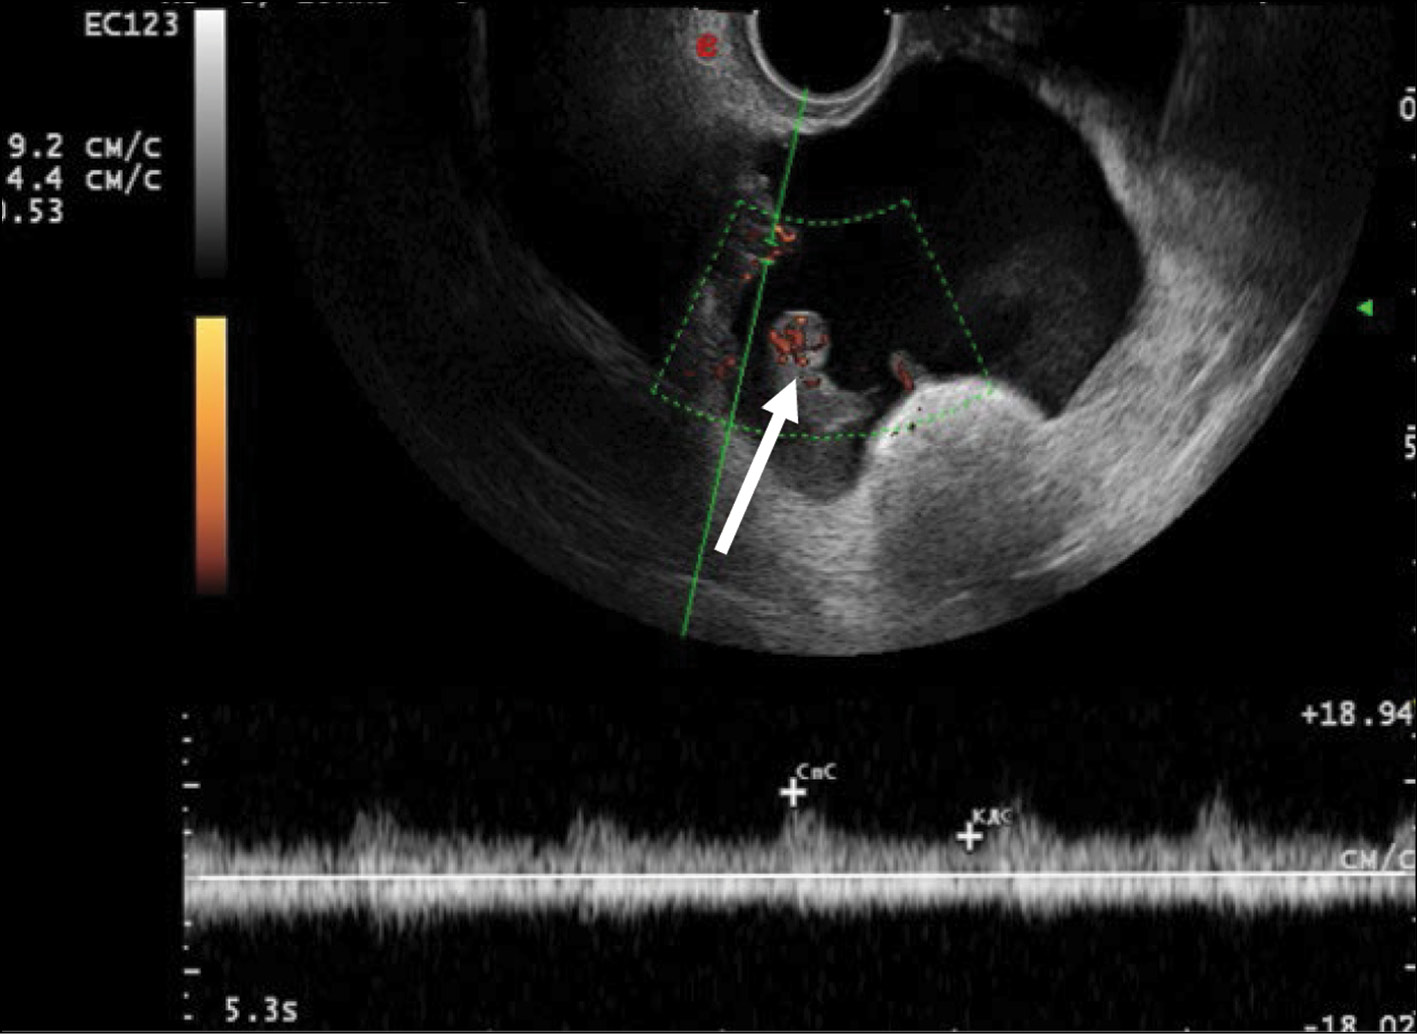

US demonstrated that the recurrent lesion of malignant struma ovarii along the pelvic peritoneum, identified in the presence of ascites, had an iso-hypoechoic structure with fuzzy contours and small size (4–12 mm). The peritoneum of the small pelvis outside the lesion was <4 mm thick; however, 3D angiography and US-CT revealed that even small blastomatous lesions were well vascularized. Blood flow was also present in the 4–5 mm thick structure of the pelvic peritoneum (Figs. 5–7).

Fig. 5. Dopplerography in the energy mode. The arrows show recurrent lesions of the malignant struma ovarii.

To identify specific US signs of malignant struma ovarii, recurrent tumor lesions along the peritoneum of the malignant struma in one patient were compared with recurrent lesions of serous ovarian adenocarcinoma in 12 patients. When comparing the tumor lesions in the retrouterine space, a more pronounced neoangiogenesis was noted in the tumor lesion of the malignant struma ovarii, where the peak systolic velocity (PS) was recorded in small lesions (4–12 mm) and ranged from 2 to 9 cm/s. The maximum vascular resistivity index (RI max) was 0.53. No blood flow was noted in recurrent lesions along the pelvic peritoneum of the serous adenocarcinoma up to 9 mm, and in lesions up to 15–20 mm, PS varied from 2 to 4 cm/s or was <2 cm/s (Figs. 5 and 8).

Fig. 8. Dopplerography (energy mode) of the tumor lesion along the peritoneum in the retrouterine space in a patient with stage IIIC serous ovarian cancer.